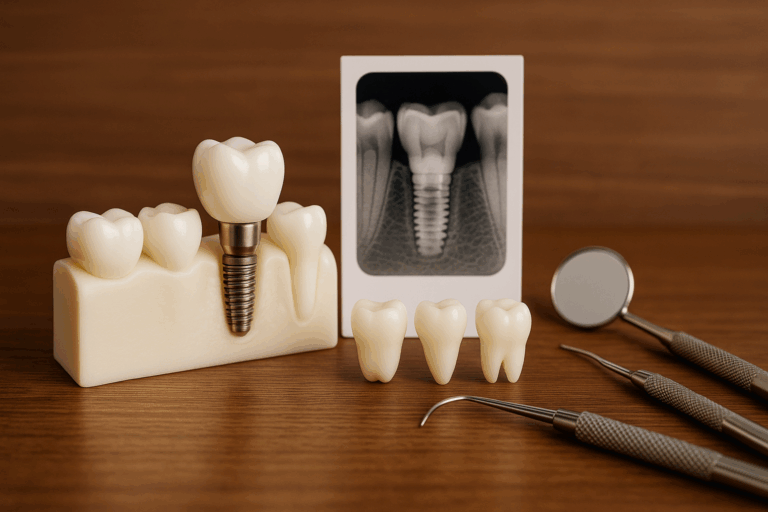

Implanty zębowe to nowoczesne i coraz częściej wybierane rozwiązanie dla osób, które utraciły swoje naturalne zęby….

Proteza na implantach w jeden dzień to nowoczesne rozwiązanie, które pozwala na szybkie odzyskanie pełnego uśmiechu….